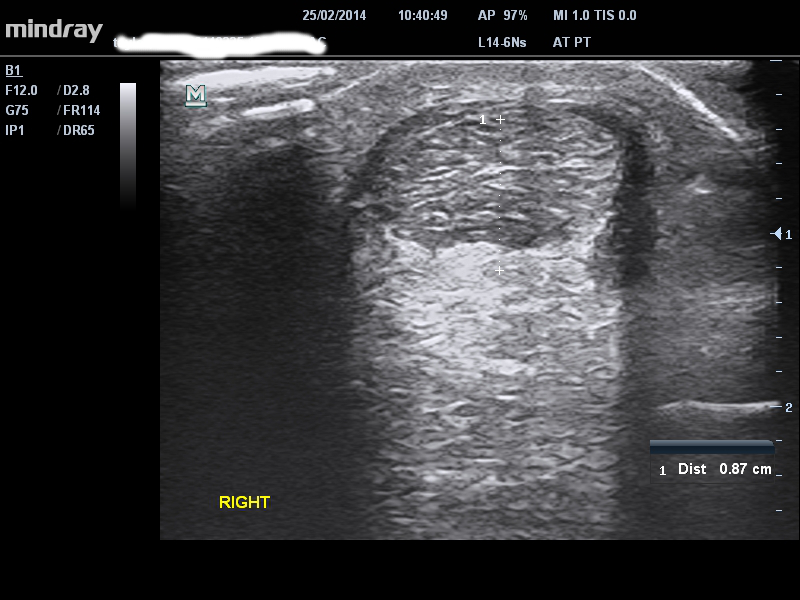

TENDINOPATIA DE LA PORCION MEDIA

Los síntomas típicos de esta condición incluyen dolor localizado del tendón de Aquiles que se “calienta” con la actividad. El dolor suele empeorar por la mañana, pero mejora después de 5-10 minutos. Por lo general, existe un historial de sobrecarga en la actividad del ciclo de estiramiento y acortamiento, como caminar o correr. Una prueba útil es la sensibilidad a la palpación en una posición estirada frente a una posición relajada (London Hospital Test). Si el tendón duele más en una posición relajada, es más probable que sufra dolor en los tendones que en los tejidos circundantes, por ejemplo: bolsa de grasa, bursa. Las imágenes en realidad no ayudan a confirmar un diagnóstico, pero pueden ser útiles para identificar el alcance de la patología – nuestro paciente presentó cambios ‘degenerativos’ menores difusos con señal Doppler, pero con dolor en la parte media. En este caso, debería tener cuidado con la carga en el rango final, aunque sus síntomas sean de proporciones medias, según el hallazgo de alguna patología de inserción baja de la porción media.

single-image

1 – patología de la porción media y de la baja porción media (cerca de la inserción) y señal de Doppler difusas